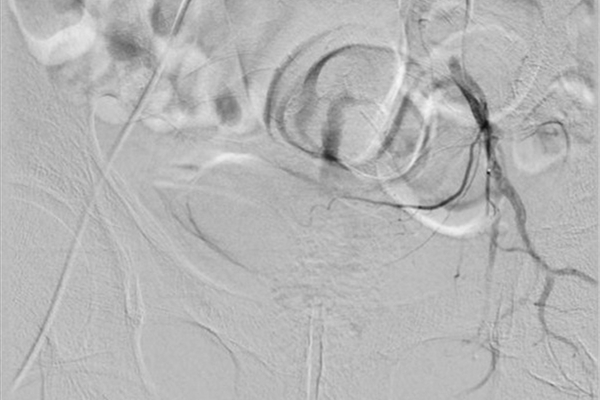

下图中,红色箭头所指为前列腺动脉,绿色箭头所指阴影部位为增生的左侧前列腺染色。